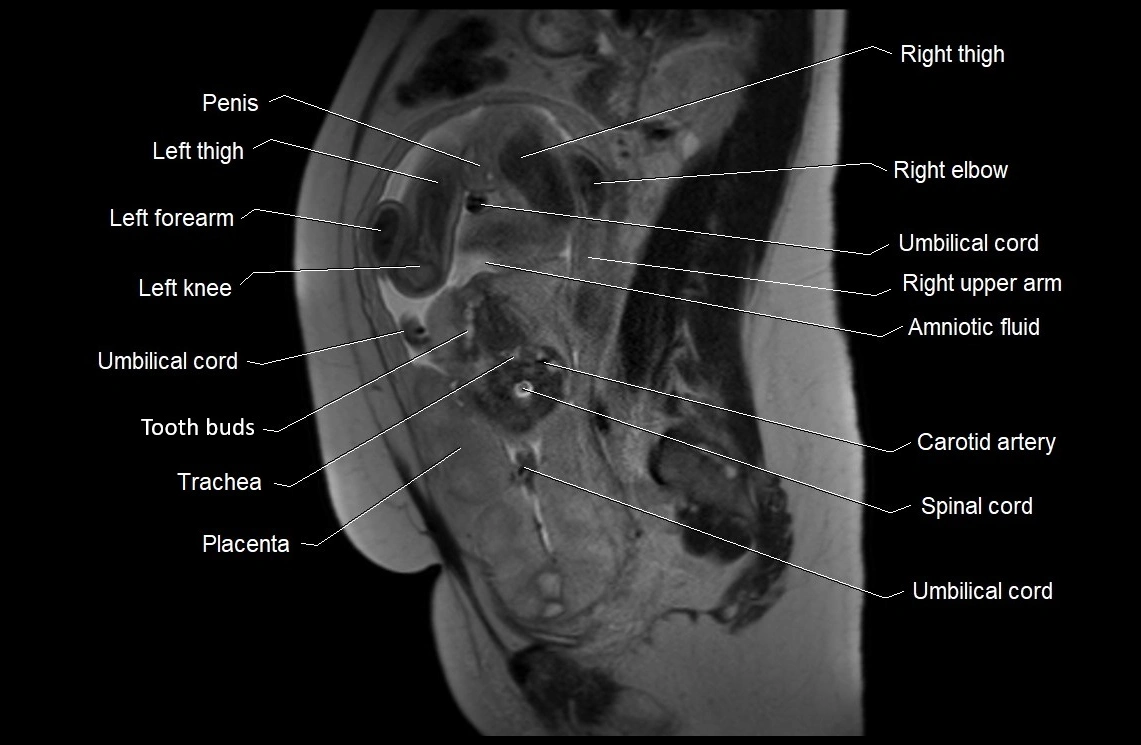

MRI Appearance

T2 HASTE (T2 GRE):

• Amniotic fluid shows very bright hyperintense signal

• Provides natural contrast against fetus and placenta

• Small particles (vernix) may appear as scattered hypointense foci within bright fluid

MRI image

image